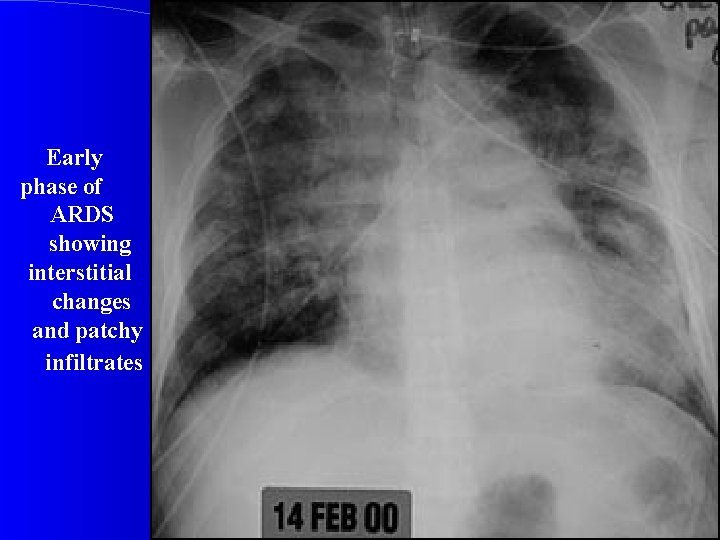

CXR Chest radiographic findings are non-specific and resemble those of typical pulmonary edema or pulmonary hemorrhage. There are diffuse bilateral coalescent opacities (the only radiological criterion defined by the Consensus Conference). The time course of ARDS may help in differentiating it from typical pulmonary edema. Chest x-ray features usually develop 12 -24 hours after initial lung insult as a result of proteinaceous interstitial edema. Within one week, alveolar pulmonary edema (hyaline membrane) occurs due to type 1 pneumocyte damage. In contrast to cardiogenic pulmonary edema, which clears in response to diuretic therapy, ARDS persists for days to weeks.

Early phase of ARDS showing interstitial changes and patchy infiltrates